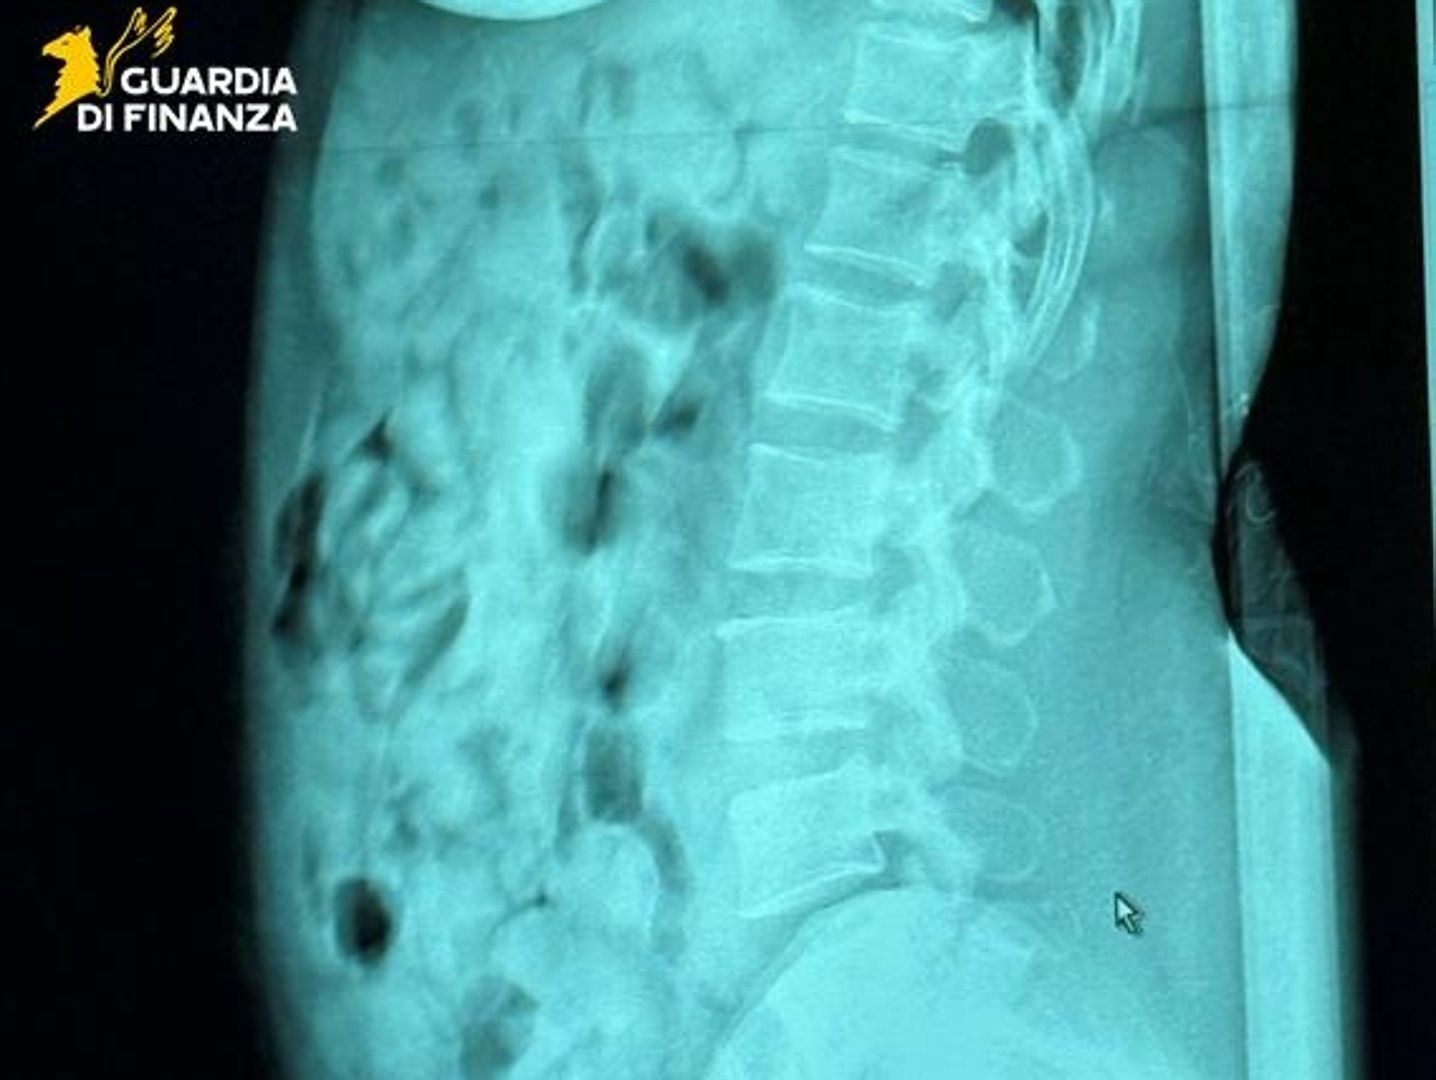

Gli esami e il sequestro

Portata all’ospedale Papa Giovanni XXIII di Bergamo, i radiologi hanno confermato la presenza degli ovuli nello stomaco. Una volta espulsi, sono risultati contenere 1,393 chili di eroina. La sostanza stupefacente è stata sequestrata, mentre la donna è stata arrestata e portata al carcere di Bergamo, a disposizione dell’autorità giudiziaria.